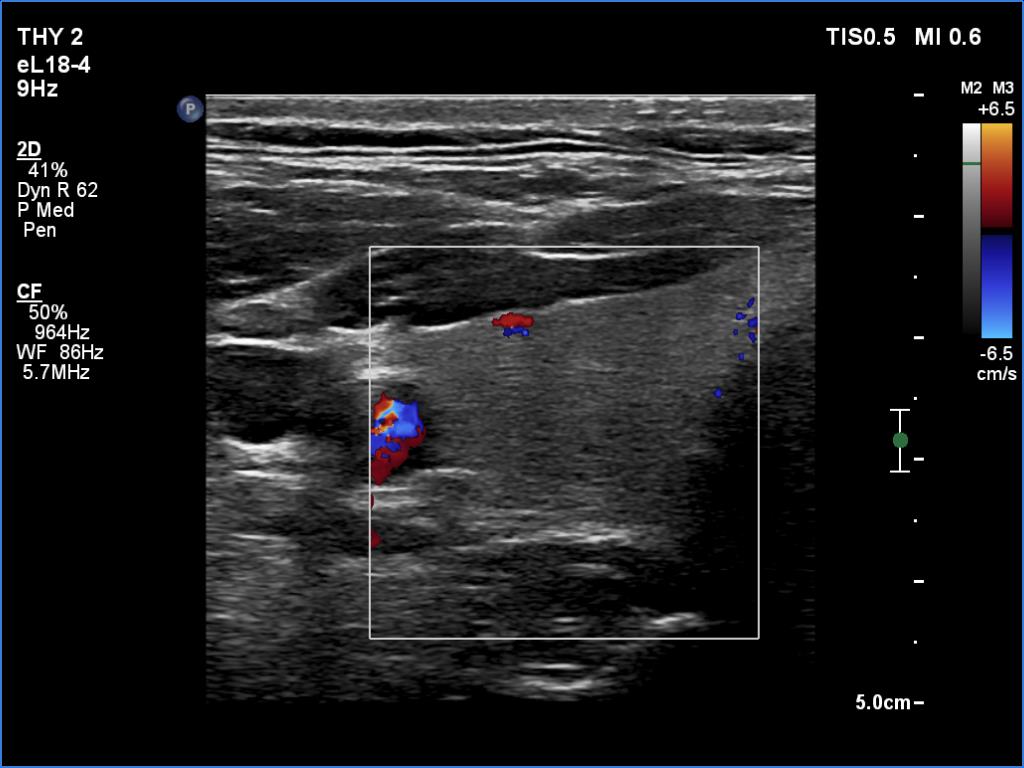

Right lobe, transverse scan, color Doppler mode. The vascularity is very scanty.